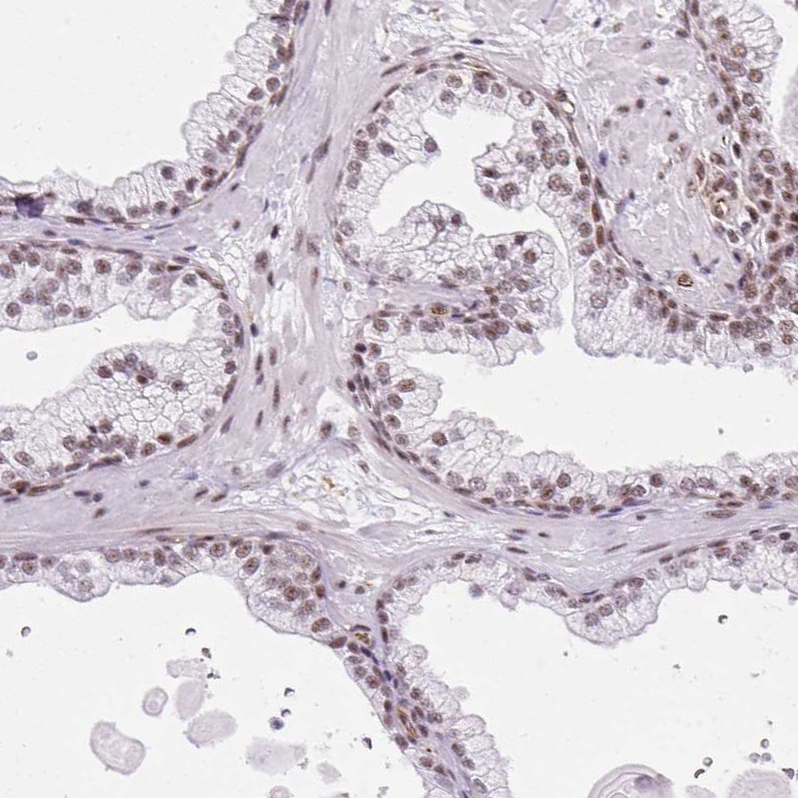

Immunohistochemical staining of human kidney shows moderate nuclear positivity in cells in tubules.